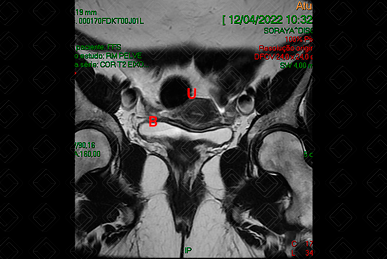

O protocolo básico da RM de pelve consiste em: T1 axial, T2 nos três planos (coronal, sagital e axial), T1 com saturação de gordura pré e T1 com saturação de gordura pós-contraste (Figuras 1, 2 e 3).

Texto alternativo para a imagem Figura 1. RM de pelve, ponderada em T2, plano coronal. Créditos: Dra. Elazir Mota - Rio de Janeiro/RJ

Texto alternativo para a imagem Figura 2. RM de pelve, ponderada em T2, plano coronal. Créditos: Dra. Elazir Mota - Rio de Janeiro/RJ

Legenda das siglas (Figuras 1 e 2): B = bexiga; O = ovários; U = útero.